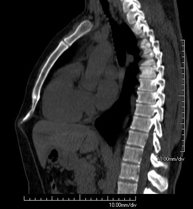

Prova diagnòstica que consisteix en l'estudi de l'abdomen d'alta definició anatòmica (fetge, vesícula biliar, via biliar, pàncrees, melsa, estómac, intestins, ronyons, estructures vasculars, bufeta, úter i ovaris, etc.) mitjançant l'ús d'un equip de TC (Tomografia Computeritzada). Aquestes imatges s'estudien posteriorment en una estació de treball que permet obtenir reconstruccions bidimensionals en diferents plànols de l'espai i també reconstruccions 3D (volumètriques). La majoria d'estudis requereixen l'ús de contrast iodat per millorar la definició de les imatges. - TC Pelvis

Prova diagnòstica que consisteix en obtenir imatges bi i tridimensionals de l'abdomen d'alta definició anatòmica (estructures òssies, estructures vasculars, fetge, pàncrees, vesícula biliar, ronyons, glàndules suprarenals, melsa, intestí prim i gros, bufeta, úter i ovaris, pròstata i vesícules seminals, urèters, etc.) mitjançant l'ús d'un equip de TC (Tomografia Computeritzada). La majoria d'estudis requereixen l'ús de contrast iodat. - TC Fetge